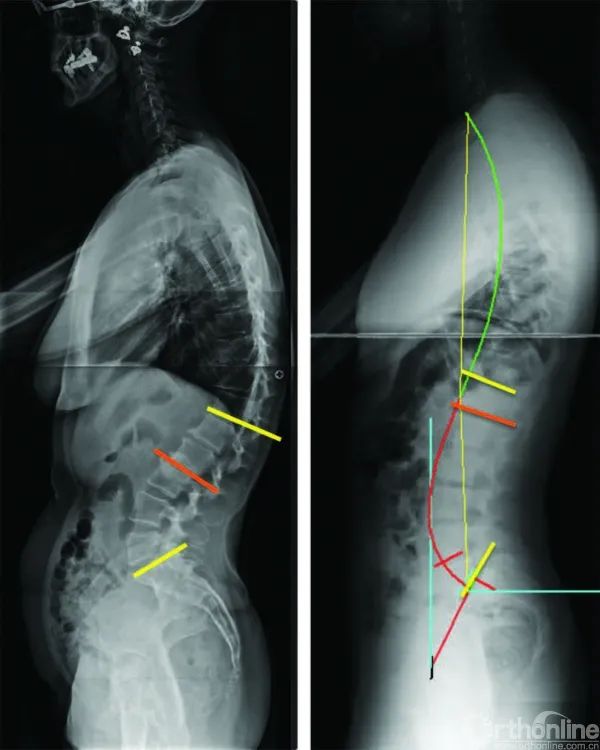

先天腰间盘突出,脊柱达到45度弯曲的人有多痛苦?

从4种腰椎前凸临界点探寻腰椎退变过程

聂新富主任医师安排患者入院后,经过仔细检查发现其腰椎生理前凸消失